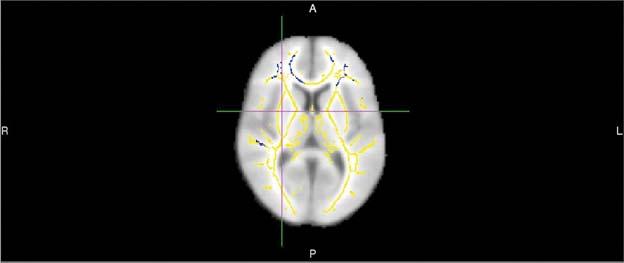

image: This image shows areas of reduced fractional anisotropy -- a diffusion MR imaging marker of white matter damage -- in 20 persons who develop Alzheimer's dementia compared to 20 who remain cognitively normal. These areas show up as blue-colored voxel overlaid onto a white matter skeleton (yellow colors) overlaid onto a standard template brain.

DTI provides different metrics of white matter integrity, including fractional anisotropy (FA), a measure of how well water molecules move along white matter tracts. A higher FA value indicates that water is moving in a more orderly fashion along the tracts, while a lower value means that the tracts are likely damaged.

About half of the patients went on to develop Alzheimer's disease, and DTI identified quantifiable differences in the brains of those patients. People who developed the disease had lower FA compared with those who didn't, suggesting white matter damage. They also had statistically significant reductions in certain frontal white matter tracts.